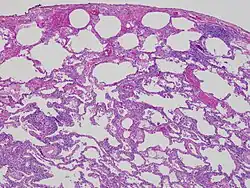

| High magnification photomicrograph of a lung biopsy taken showing chronic hypersensitivity pneumonitis (H&E), showing mild thickening of the walls of the small air sacs by invasion of white blood cells. A multinucleated giant cell, seen within the walls of the air sacs to the right of the picture halfway down, is an important clue to the correct diagnosis. | |

Lung biopsy

Lung biopsies can be diagnostic in cases of chronic hypersensitivity pneumonitis, or may help to suggest the diagnosis and trigger or intensify the search for an allergen. The main feature of chronic hypersensitivity pneumonitis on lung biopsies is expansion of the interstitium by lymphocytes accompanied by an occasional multinucleated giant cell or loose granuloma.[7][22]